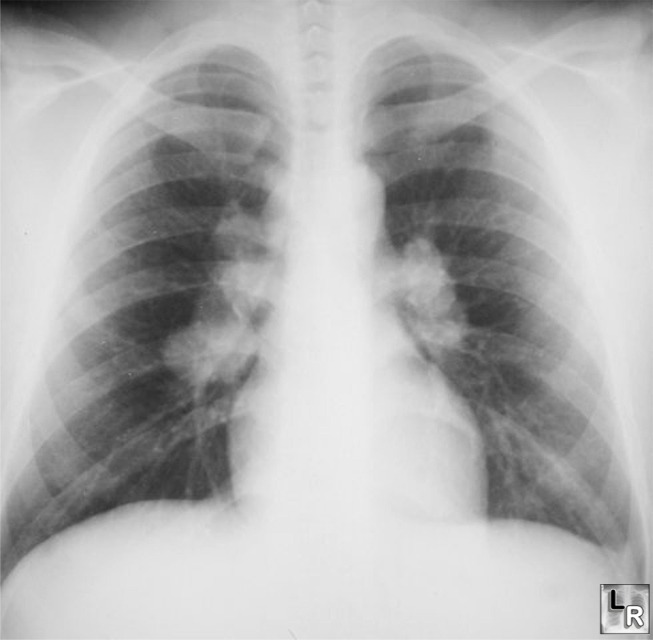

Olgu: 34 yaşında, 1. Sınıf tıbbi sertifikası olan siyahi pilot. Bir hava kargo şirketinde çalışıyor. 6 haftadır devam eden öksürük, dispne, kilo kaybı, miyalji ve kırgınlık şikâyetleri var. Hastalığı birinci basamak hekimi tarafından reçetelenen çeşitli antibiyotik rejimlerine direnç göstermiş ve Şubat 1996′da konsültasyon için göğüs hastalıkları uzmanına yönlendirilmiş. Fizik muayenesi, her iki akciğerin bazallerinde rallerin duyulması dışında normal limitlerde. Kardiyolojik muayenede, nabız sayısı normal, ritmi düzenli bulunmuş, anormal kalp sesine rastlanmamış. Cilt lezyonları yok. Ekokardiyogram normal sınırlarda, ejeksiyon fraksiyonu %60. EKG normal. Göğüs filminde hiler lenfadenopatileri ve parankimde pulmoner infiltrasyonları var. Fiberoptik bronkoskopi ve trakeobronşiyal biyopsi, mantar ve bakteriler yönünden negatif olan, sarkoidozla uyumlu nonkazeöz granülomlar ortaya koymuştu. Solunum fonksiyon testlerinde (SFT) zorlu vital kapasite (FVC) 2,4 L (beklenen değerin %51′i) ve FEV1 2,63 L (beklenen değerin %58′i) idi. 40 mg prednizon, öksürüğü ve eforla gelen dispneyi hemen hemen kesmişti. Sonraki 4 ayda hastaya uygulanan oral prednizon tedavisi, semptomlarına göre azaltılarak devam etti.

Klinik Bulgular: En yaygın klinik belirti, özellikle genç erişkinlerde hastaların %50’sinde olan ve sıklıkla rutin akciğer grafisinde saptanan bilateral hiler lenfadenopatidir. Yaklaşık %25′i bilateral hiler lenfadenopati ve pulmoner infiltrasyonlarla, %15′i tek başına infiltrasyonla görülür. Akciğer hilumundaki hastalık, bronşların invazyonu veya kompresyonuyla ya da nodal kalsifikasyonla ilişkili değildir. Eritema nodozum veya üveit (kırmızı ve sulanmış göz) ile kendini gösterir; hiler adenopatiye eşlik edebilir. Bazı hastalarda öksürük, nefes darlığı, wheezing ve göğüste rahatsızlık hissi, (bu pilotta olduğu gibi) ateş, kırgınlık ve yorgunluğa ek olarak görülebilir. Pulmoner semptomlar en sık olmasına rağmen, hepatomegali, splenomegali veya üveit gibi toraks dışı organ hastalığı da görülebilir. Diğer başvuru nedenleri; sebebi bilinmeyen ateş, granülomatöz hepatit, artrit, periferal lenfadenopati ve cilt lezyonlarıdır.